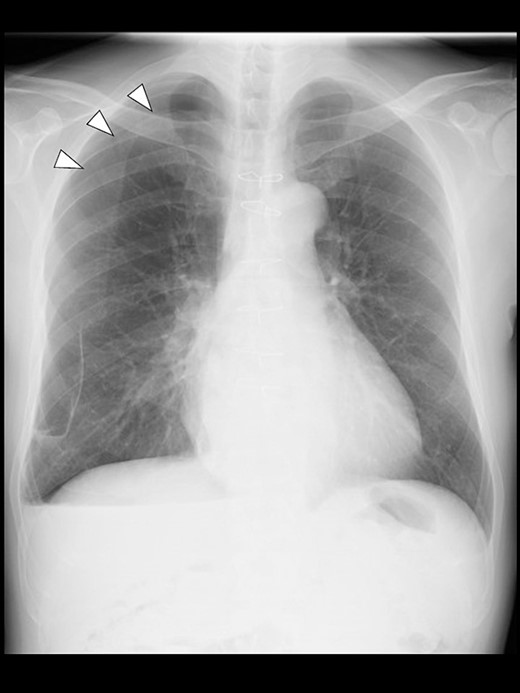

Even though the patient did not receive supplemental oxygen in the ward, SpO2 remained at 98%. Chest radiographs were not taken on the day of surgery. However, a chest radiograph taken in the upright position on postoperative Day (POD) 1 revealed a pneumothorax on the right side (Fig. 2), although he had no respiratory symptoms. Radiographs on PODs 2 and 3 revealed the pneumothorax remaining unchanged (Fig. 3). The patient was discharged from the hospital on POD 3 without any respiratory symptoms. A chest radiograph taken on POD 19 showed no remaining pneumothorax.

A chest radiograph in the upright position on POD 3 showing a residual right pneumothorax (arrowheads).